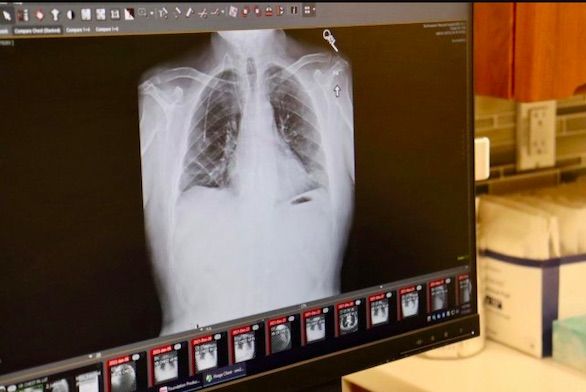

أعلن أطباء في مستشفى نورث وسترن ميديسن، بمدينة شيكاغو الأمريكية، بأنهم أجروا عملية هي الأولى من نوعها تم خلالها زرع رئتين بنجاح لمريض مصاب بسرطان الرئة.

من جهته قال الدكتور أنيكت بهارات، وهو أحد الجراحين الذين أجروا العملية ورئيس قسم جراحة الصدر في المستشفى، في بيان صحفي: ” بالنسبة للمرضى الذين يعانون من سرطان الرئتين في المرحلة الرابعة، فإن عملية زراعة الرئة غير ممكنة، ولكن لحسن حظ ألبرت أن السرطان كان محصوراً في صدره، وكنا واثقين من قدرتنا على التخلص من السرطان أثناء الجراحة وإنقاذ حياته”

على الرغم من أن عمليات زرع الرئة أصبحت أكثر شيوعًا لدى الأشخاص المصابين بالنوع المميت من السرطان، إلا أن إجراءها اقتصر على الأشخاص الذين لم يصلوا بعد إلى المرحلة الرابعة من السرطان، حيث تنتشر الأورام في الرئتين وأعضاء أخرى من الجسم، ولكن في حالة ألبرت فكان الوضع مختلفاً حيث اقتصرت الأورام على صدره رغم وصول المرض إلى المرحلة الرابعة.

ومع ذلك، استمرت صحة ألبرت في التدهور، وانتهى به المطاف في وحدة العناية المركزة على جهاز التنفس الصناعي مع التهاب رئوي وتعفن الدم، مما دفع الأطباء لإجراء تقييم لحالته، وتبين بأنه مؤهل للحصول على رئتين جديدتين لأن الورم كان موضعياً في الصدر ولم ينتشر إلى أجزاء أخرى من جسده وهو أمر نادر الحدوث في المرحلة الرابعة من السرطان.

حصل ألبرت على رئتيه الجديدتين في 25 سبتمبر، وبعد ستة أشهر من العملية، لم يعد بحاجة إلى دعم الأكسجين للتنفس و بدأ بممارسة حياته بشكل طبيعي.